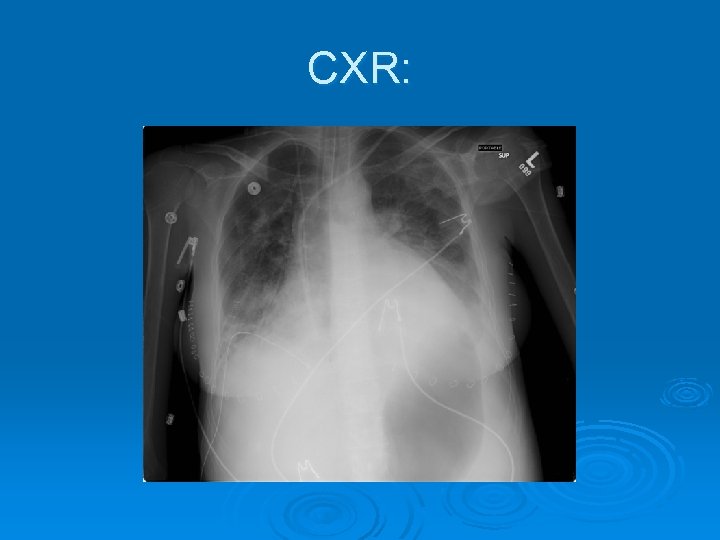

CXR: